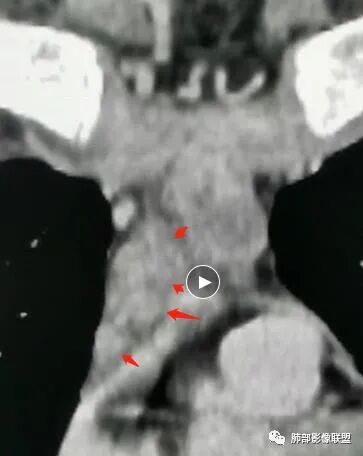

空格: 部分结节DWI高,T2有积液,不符合胸腺增生,还是淋巴瘤优先考虑。CT增强有环形强化。但DWI病灶中央也亮的,结核可能不大。

炎症:符合点——强化、周围边界不清,白介素6高,但是没症状,DWI中央低强化区不高

DWI好像中央高一些

看这个图

空格: 看到的结节其实还是增生结节,为什么t2有积液,是伴发了脓肿、感染

必有路: 还有坏死区域部分弥散受限

常规会考虑到tb  其他的炎症,还是少见 ,不太优先考虑肿瘤

周边模糊,中央坏死,弥散受限

炎性特点是有的  只是常规会考虑tb  至于化脓性淋巴结炎,症状太轻,没常规考虑